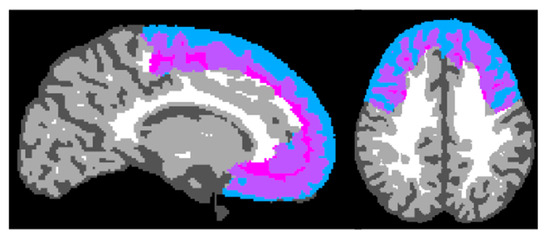

3.6. Frontal Lobe GMV